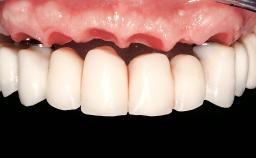

Immediate Loading of Six Implants in the Maxilla and Final Restoration with a Full-Arch Gold/Ceramic FDP Involving the Concept of Tilted Implants

Prosthesis Type FDP